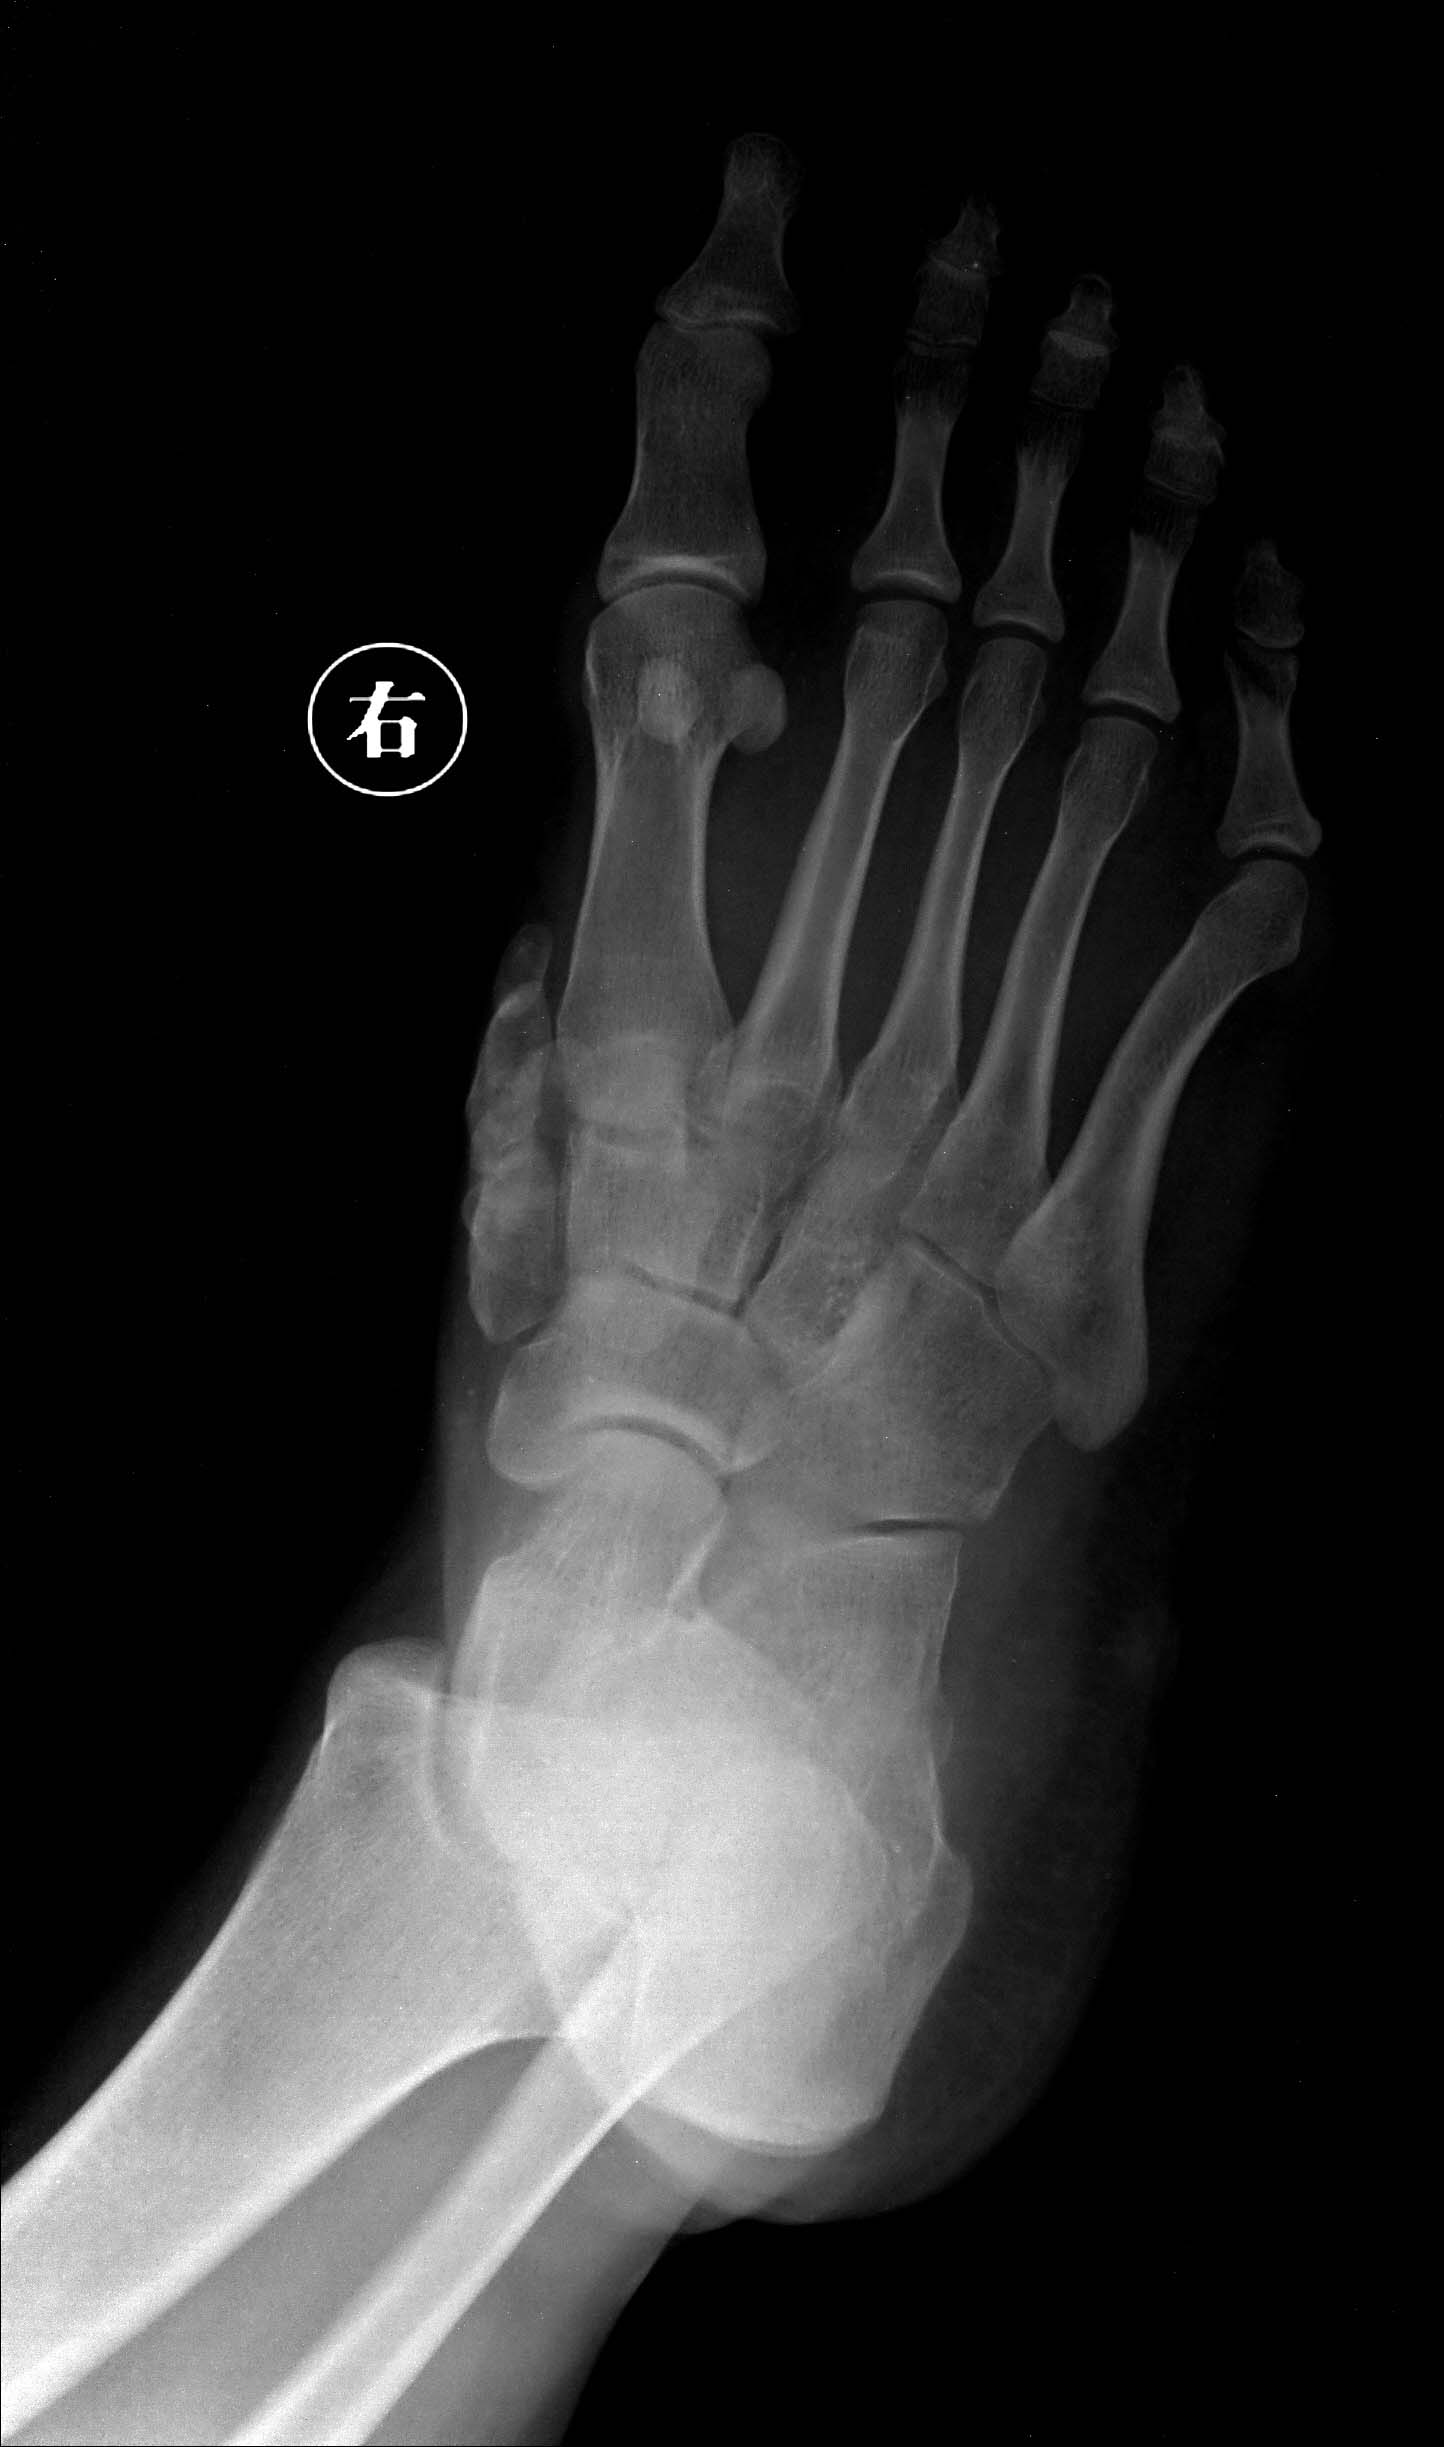

跖骨远端骨折伴跖趾关节脱位非手术治疗方法